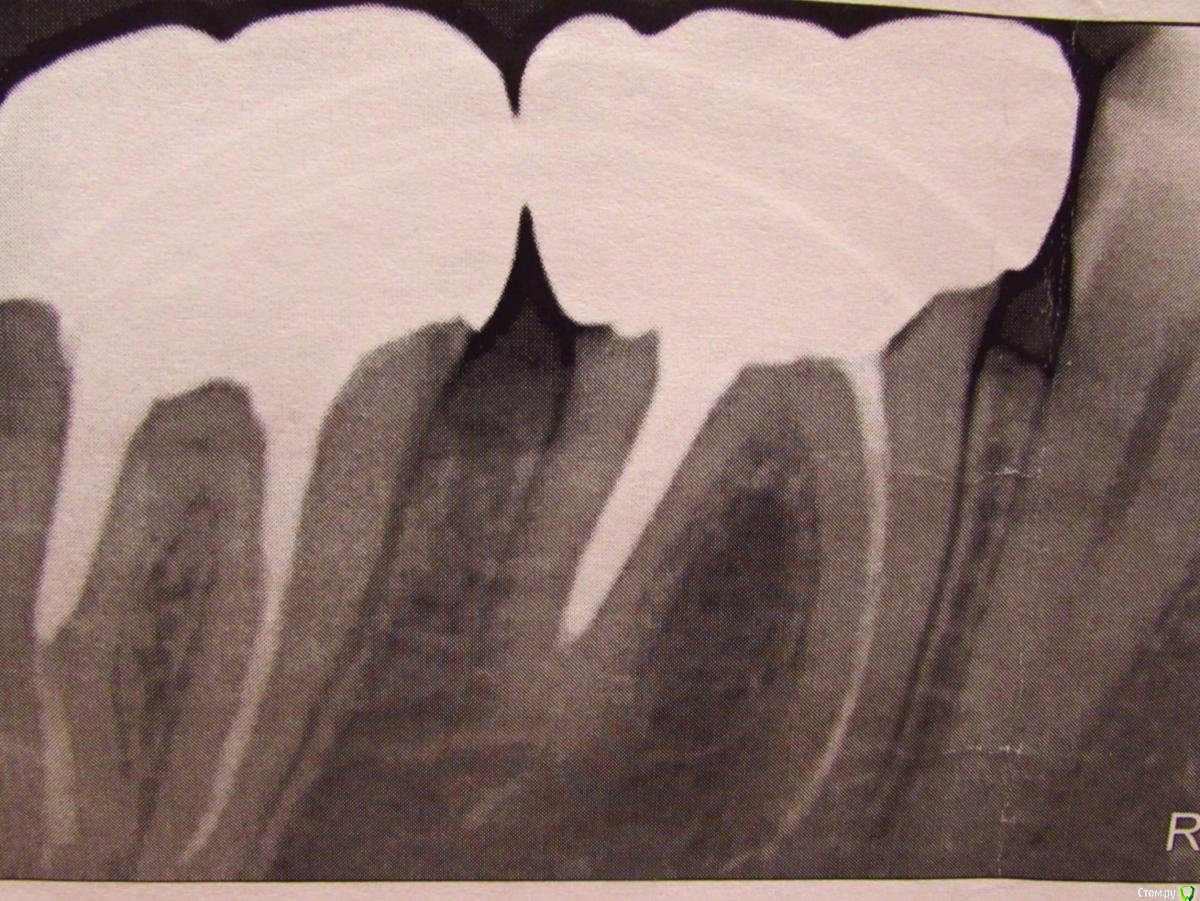

Подскажите, пожалуйста, действительно ли бывает такой пломбировочный материал для коней, который не виден на рентгеновских снимках? Я делала протезирование коронками с металлическими культевыми вкладками. Когда примеряли вкладки, доктор спиливал длинную "ножку". Зачем он изначально сделал ее именно такой длинной не знаю. Но стало быть под эту "ножку" был убран пломбировочный материла из канала. После окончания работ я попросила сделать контрольный снимок. Сделали. И я увидела, что канал пустой. Я спросила доктора, почему канал пустой. На это он мне ответил (как мне показалось, заметно нервничая), что канал не пустой, а там есть материла (или цемент, не помню точно), но его просто не видно на снимке. Вот такой рентгенонейтральный, что-ли материал. У меня есть поводы беспокоится или доктор говорит правду? На первом снимке зуб до ортопедических работ. Спасибо.